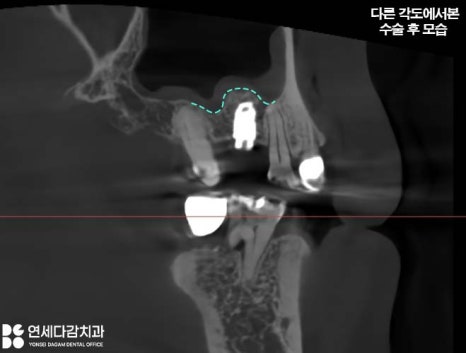

측방 접근법으로 진행할 시에는

막을 조심스럽게 손상 없이 거상한 후

그 공간에 뼈이식재를 채워 차폐막으로 덮고

가능하다면 임플란트 식립까지 진행하여

마무리합니다.

이렇게 잔존골 상태에 따라

임플란트를 동시에 식립하거나

골이식 후 4~6개월 치유 기간을

가진 뒤에 임플란트를 식립하기도 합니다.

치유 기간

오금역 치과 에서 설명드린

측방 접근법으로 진행한 뒤에는

보통 4~6개월 정도의 치유 기간 후

보철 과정을 진행하게 됩니다.